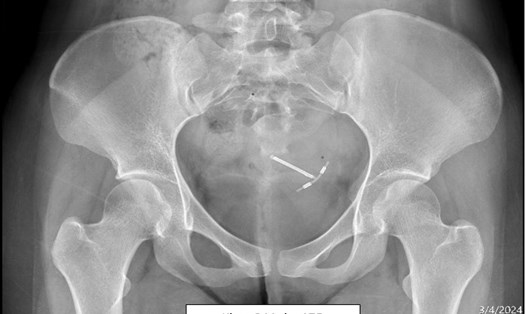

Lấy vòng tránh thai lạc trong ổ bụng, đâm xuyên tử cung của 2 phụ nữ

NGUYỄN LY |

TPHCM - Vừa qua, Bệnh viện Quân y 175 đã thực hiện phẫu thuật nội soi lấy vòng tránh thai lạc chỗ trong ổ bụng cho 2 nữ bệnh nhân.